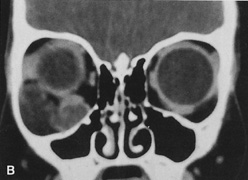

Valuable information about the nature and extent of an orbital pathologic process is provided by imaging studies such as computed tomography (CT) scan, magnetic resonance imaging (MRI), and orbital echography. Better spatial resolution, ready accessibility, and lower cost make CT the preferred choice for orbital imaging in most cases. Orbital fat provides a natural contrast between most adjacent orbital structures on CT scanning, and orbital bones are visualized well. Computed tomography is essential for evaluation of the orbital bones because they cannot be imaged with MRI. Direct coronal or sagittal images are important to identify the relationship of a lesion to the optic nerve so that the surgical approach can be planned to avoid traversing the optic nerve (Fig. 1).

Fig. 1. A. Axial CT scan demonstrating a large, well-encapsulated lesion in the orbital apex. Coronal (B) and sagittal (C) scans demonstrate that the mass lies inferior and medial to the optic nerve within the intraconal space. This information is useful in planning the surgical approach to the mass, which should avoid traversing the optic nerve.